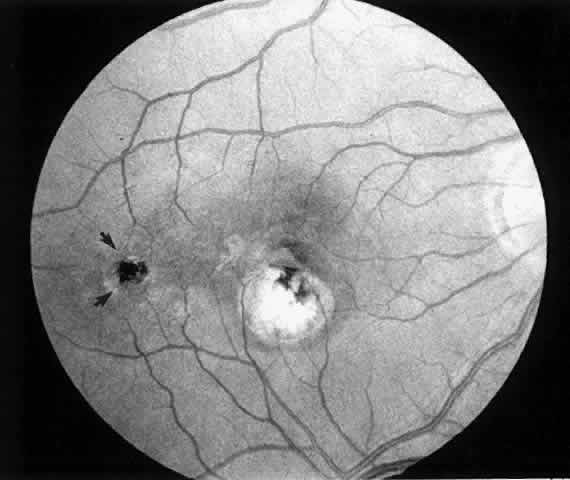

Fig. 10. Postoperative fundus photograph (case 2). One year after surgery, visual acuity is 20/20 (6/6). Note laser scar at retinotomy site (arrows).

2. A 35-year-old patient developed an idiopathic subfoveal choroidal neovascular membrane with decrease in vision to 20/200 (6/60) (Fig. 9). He underwent surgical excision of the membrane. Laser was applied to the retinotomy at the conclusion of the case. One year after surgery, his visual acuity remained stable at 20/20 (6/6) (Fig. 10).